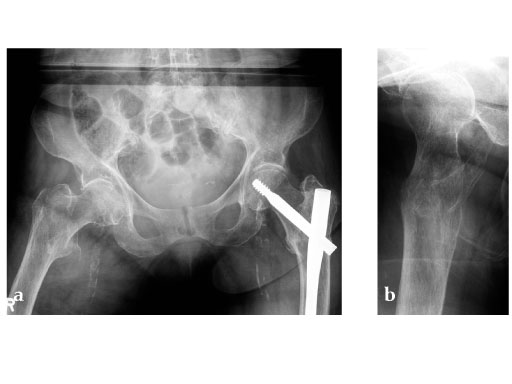

Ten pairs of human cadaveric femora were used. Left and right bones of every femoral pair were randomly instrumented with either a DHS blade or a DHS using 4-hole side plates. Tip-apex distance was standardized to 10 mm. After implantation an unstable type 31-B2 fracture (Fig 1) was created using a custom-made saw guide. Cyclic loading was performed to the femoral head applying load trajectories as measured in vivo in total hip replacement (THR) patients (Bergmann et al., 2001). The passive function of the iliotibial band was simulated by a cable. Starting at 1500 N the peak load was increased by 500 N every 5000 cycles until cut-out or complete failure of the construct. X-rays were taken at 5000 cycle intervals. A survival analysis was performed based on the numbers of cycles until cut-out, defined as the first visible implant migration as determined from x-rays.

Müller AO Classification type 31-A2 fracture in an 83 year-old female with severe osteoporosis.